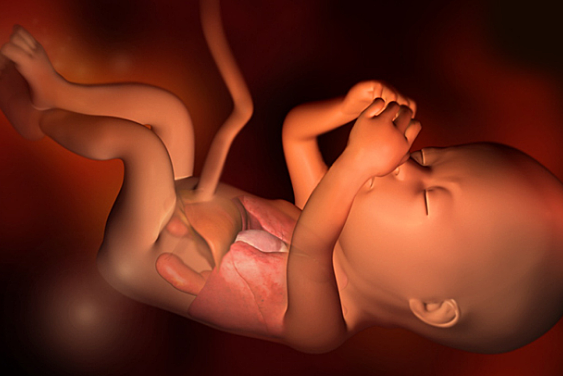

En la semana 31 de embarazo, pesa entre 1.600 y 1.700 gramos aproximadamente y mide alrededor de 41-42 centímetros. Alrededor de la semana 31 de gestación, los bebés suelen colocarse ya en posición cefálica, la más idónea para nacer y si eso ocurre notarás ya sus movimientos en la parte alta del abdomen.

• Semana 32

Semana 32

El bebé pesa en la semana 32 de embarazo entre 1,8 y 2 kilos aproximadamente, y mide entre 38 y 43 centímetros. Ahora se cree que el bebé dentro del útero puede pensar, e incluso crear su primer recuerdo a partir de la semana 32.